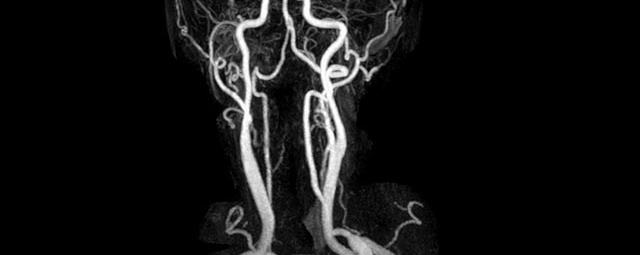

- MR-Angiografie ohne Kontrastmittel

- Time of Flight (TOF)-Angiographie

- Phasenkontrastangiographie (PCA). Geeignet zur Quantifizierung Stenose-/Insuffizienzgrad z.B. bei Herzklappen, falls echokardiographisch die Untersuchungsbedingungen eingeschränkt sind.

Je nach Fragestellung und Körperregion Gefäßdarstellung ohne Kontrastmittel bei Kontrastmittelunverträglichkeit oder terminaler Niereninsuffizienz möglich.

- MR-Angiographie mit Kontrastmittel

- Erfassung arterieller und venöser Gefäße/Bypässe aller Körperregionen mit 3D-Rekonstruktion

- je nach klinischer Fragestellung zeitaufgelöste MR-Angiographie (4D-MRA) z.B. bei Frage arteriovenöse Fistel/ Shunt oder Darstellung Unterschenkelarterien vor geplanter Bypassoperation.